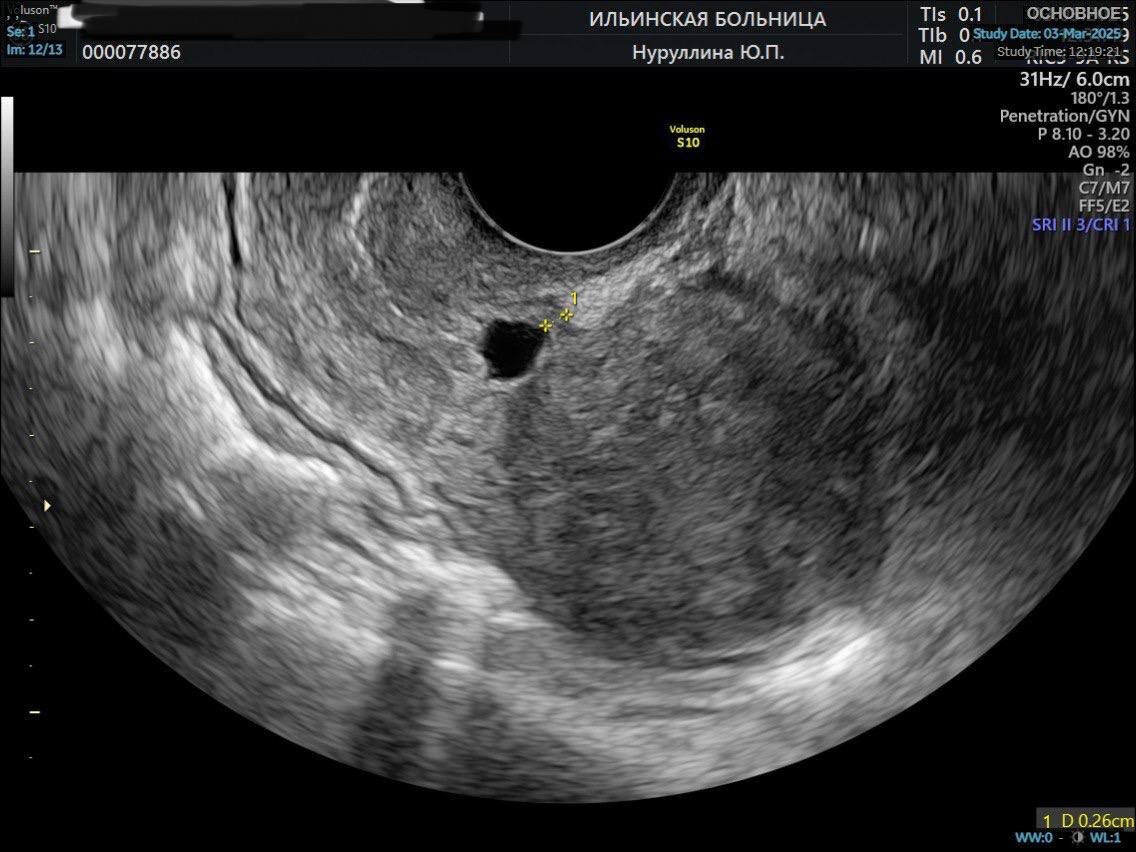

УЗИ матки до операции

Если женщина планирует беременность, крайне важно точно измерить толщину резидуального (оставшегося целого) миометрия (мышечного слоя стенки матки).

При выявлении истончения миометрия менее 3 мм над рубцом и наличии у женщины репродуктивных планов необходимо выполнить операцию — метропластику. Это лапароскопическое (через проколы в брюшной стенке) иссечение старого истончённого рубца на матке с наложением новых швов и формированием нового состоятельного рубца.

Пациентка приехала к нам из другой страны. Ей 27 лет. У неё была 1 беременность, которая закончилась операцией кесарева сечения. Спустя несколько лет пациентка приняла решение о повторном планировании беременности, и при обследовании перед планированием по данным УЗИ у неё выявлены признаки ниши в области рубца на матке.